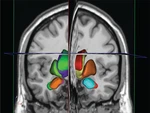

Prisys Biotechnologies telah memasang platform pengiriman obat berpemandu gambar terkemuka, yang pertama di Tiongkok, untuk mengoptimalkan pengiriman gen, sel, dan terapi lain yang sedang diselidiki langsung ke parenkim otak untuk aplikasi pra-klinis. Dengan sistem pencitraan MR internal Prisys, teknologi baru ini menggabungkan perangkat keras dan perangkat lunak khusus yang kompatibel dengan MRI untuk merencanakan lintasan bedah dan memandu kanula infus untuk mencapai sasaran. Penargetan dan pemberian dosis dapat dioptimalkan selama prosedur invasif minimal ini untuk meningkatkan keamanan dan kemanjuran.

Sistem ClearPoint® merevolusi bidang bedah saraf dengan memberikan panduan MRI intraprosedural, sehingga menghasilkan akurasi dan presisi yang tak tertandingi dalam pemberian terapi ke otak.

Sistem ClearPoint adalah cara yang aman, efisien, dan andal untuk memberikan terapi baru pada struktur tertentu di otak dengan bantuan pemetaan MR-otak yang terintegrasi. Akumulasi studi kasus pada pasien manusia dan hewan percobaan besar, dan bukti klinis yang kaya telah membuktikan keefektifannya sehingga menjadi solusi utama untuk penelitian dan pengembangan translasi dari terapi yang relevan, seperti Molekul Kecil, Biologi, Terapi Sel dan Gen, Partikel Nano, dan Asam Nukleat. Terapi berbasis. Keuntungan utama meliputi: